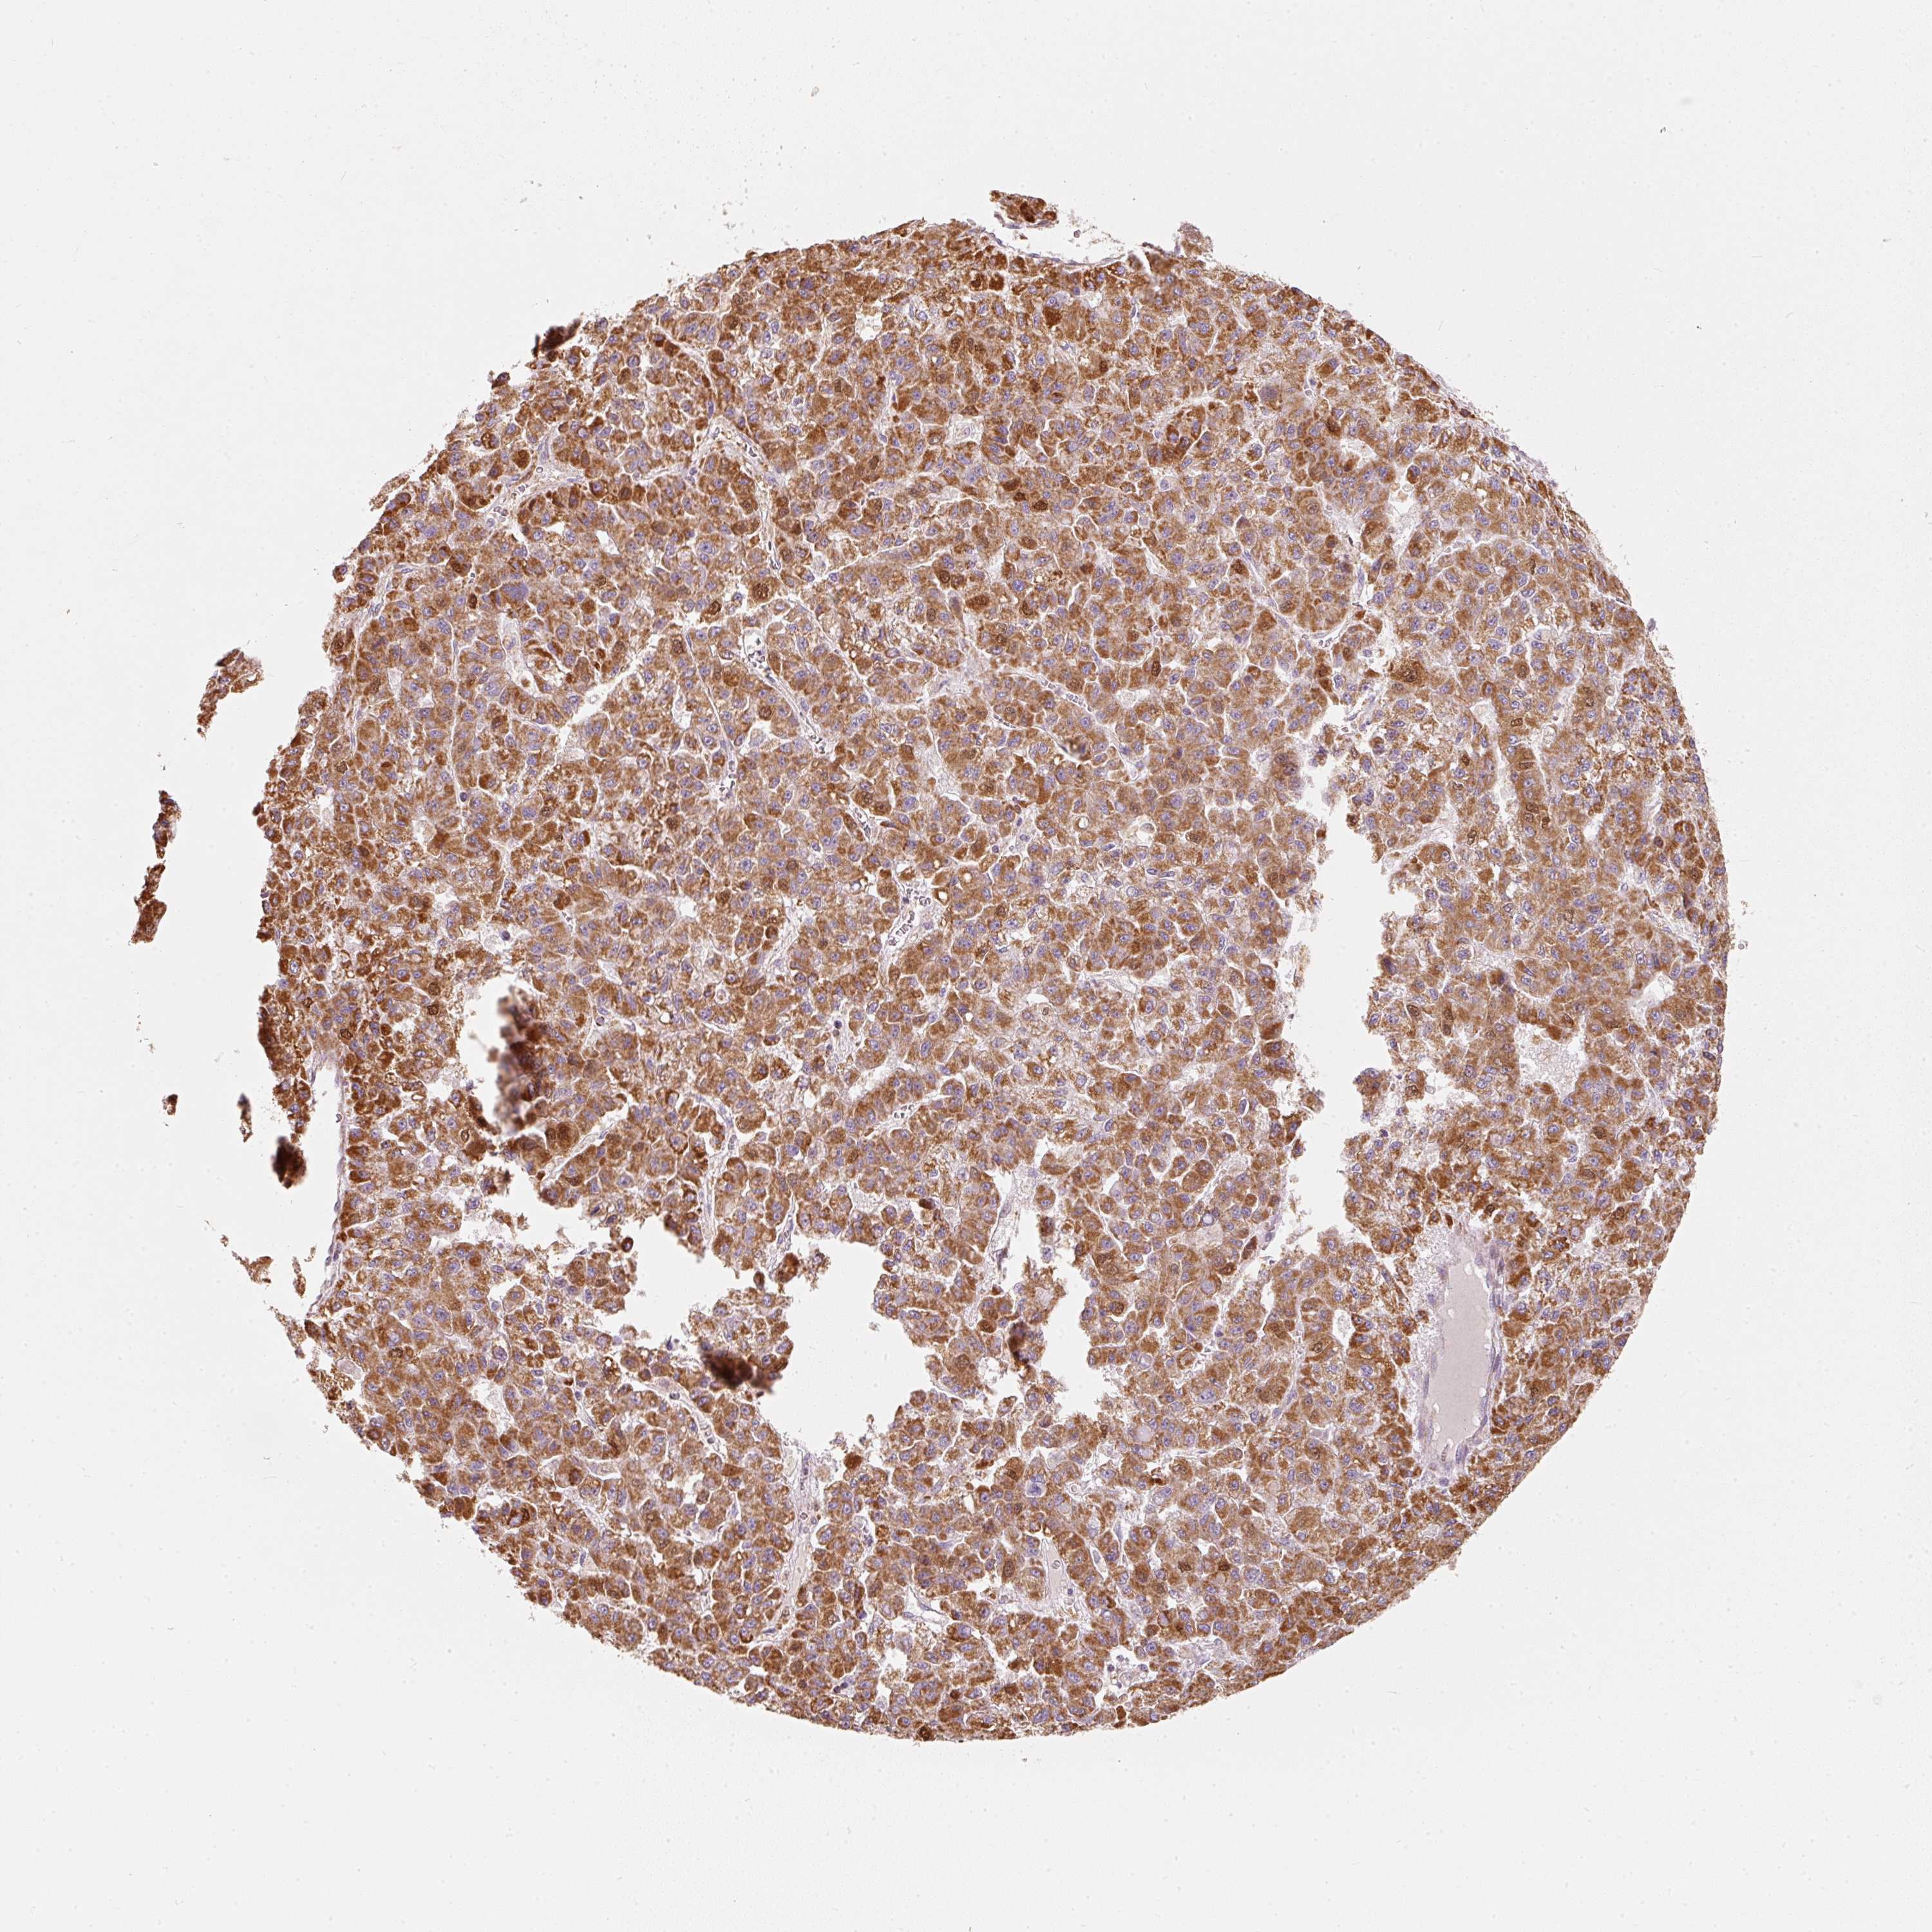

LIVER CANCER - Protein expressioni

A mouse-over function shows sample information and annotation data. Click on an image to view it in a full screen mode. Samples can be filtered based on level of antibody staining by selecting one or several of the following categories: high, medium, low and not detected. The assay and annotation is described here.

Note that samples used for immunohistochemistry by the Human Protein Atlas do not correspond to samples in the TCGA dataset.

Antibody stainingi

Antibody staining in the annotated cell types in the current human tissue is reported as not detected, low, medium, or high, based on conventional immunohistochemistry profiling in selected tissues. This score is based on the combination of the staining intensity and fraction of stained cells.

Each image is clickable and will lead to virtual microscopy that enables deeper exploration of all samples and also displays staining intensity scores, fraction scores and subcellular localization as well as patient and tissue information for each sample.

Antibody HPA054422

Antibody HPA060360

Staining

High

Medium

Low

Not detected

Intensity

Strong

Moderate

Weak

Negative

Quantity

>75%

75%-25%

<25%

None

Location

Nuclear

Cytoplasmic/membranous

Cytoplasmic/membranous,nuclear

Carcinoma, Hepatocellular, NOS

Cholangiocarcinoma